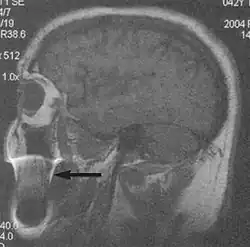

Metal artifacts

Metal artifacts occur at interfaces of tissues with different magnetic susceptibilities, which cause local magnetic fields to distort the external magnetic field. This distortion changes the precession frequency in the tissue leading to spatial mismapping of information. The degree of distortion depends on the type of metal (stainless steel having a greater distorting effect than titanium alloy), the type of interface (most striking effect at soft tissue-metal interfaces), pulse sequence and imaging parameters. Metal artifacts are caused by external ferromagnetics such as cobalt containing make-up, internal ferromagnetics such as surgical clips, spinal hardware and other orthopaedic devices, and in some cases, metallic objects swallowed by people with pica.[3] Manifestation of these artifacts is variable, including total signal loss, peripheral high signal and image distortion (Figs 3 and 4).[1] Reduction of these artifacts can be attempted by orientating the long axis of an implant or device parallel to the long axis of the external magnetic field, possible with mobile extremity imaging and an open magnet. Further methods used are choosing the appropriate frequency encoding direction, since metal artifacts are most pronounced in this direction, using smaller voxel sizes, fast imaging sequences, increased readout bandwidth and avoiding gradient-echo imaging when metal is present. A technique called MARS (metal artifact reduction sequence) applies an additional gradient, along the slice select gradient at the time the frequency encoding gradient is applied.